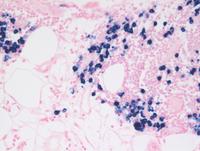

H&E images showing upper and deep dermal lymphoid infiltrate present patchily investing the follicular infundibulum at places on higher power. The constituent cells comprise small lymphoid cells few plasma cells, immunoblasts and clusters of histiocytes.

In situ hybridization for kappa and lambda immunoglobulin light chain shows markedly increased numbers of kappa positive plasmacytic cells associated with the background lymphoid cells with very few lambda positive cells, indicative of kappa light chain restriction within the plasmacytic cells.